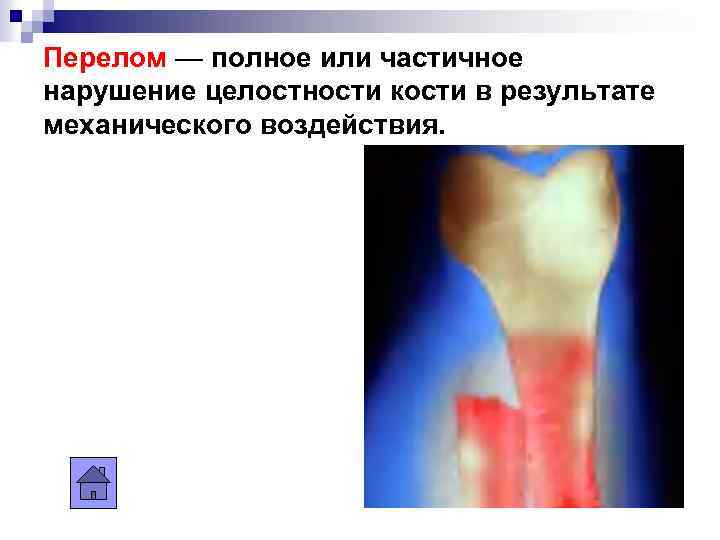

Перелом — полное или частичное нарушение целостности кости в результате механического воздействия.

Перелом — полное или частичное нарушение целостности кости в результате механического воздействия.